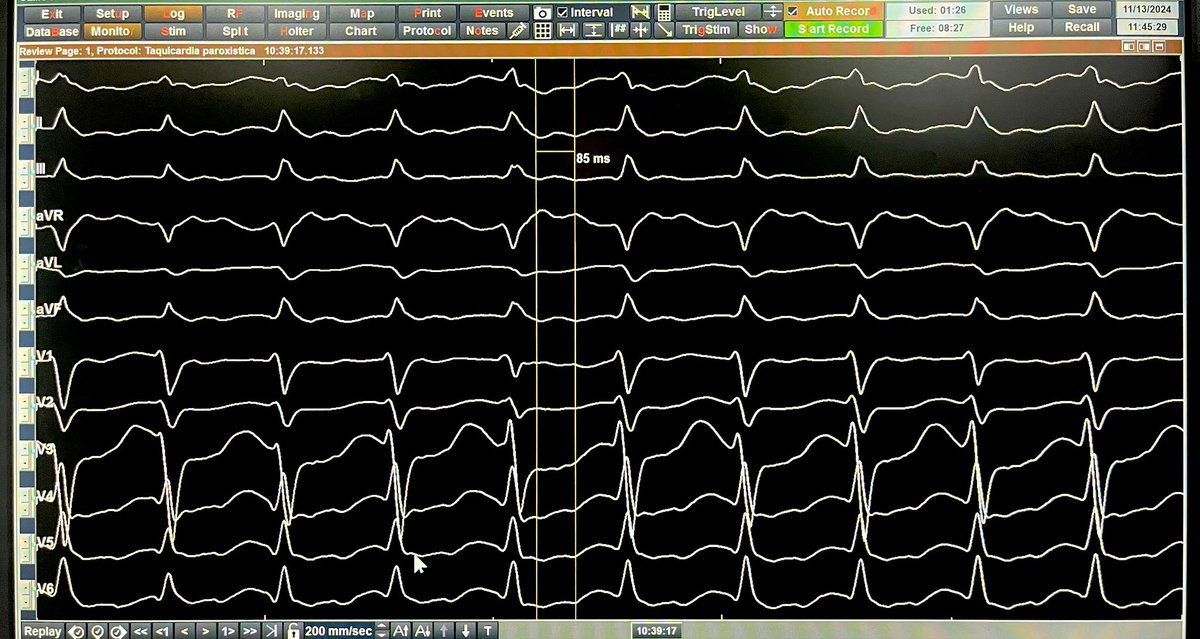

45 yo male, morbid obesity w/ PMHx of WPW syndrome & documented regular WCT. Antidromic Reentrant tachycardia (ART) using a left lateral AP as anterograde limb & AVN as retrograde limb. Duodromic tach w/presence of septal AP r/o w/pacing maneuvers Retro AV conduction 260 ms

45 yo male, morbid obesity w/ PMHx of WPW syndrome &amp; documented regular WCT.

Antidromic Reentrant tachycardia (ART) using a left lateral AP as anterograde limb &amp; AVN as retrograde limb.

Duodromic tach  w/presence of septal AP r/o w/pacing maneuvers

Retro AV conduction 260 ms